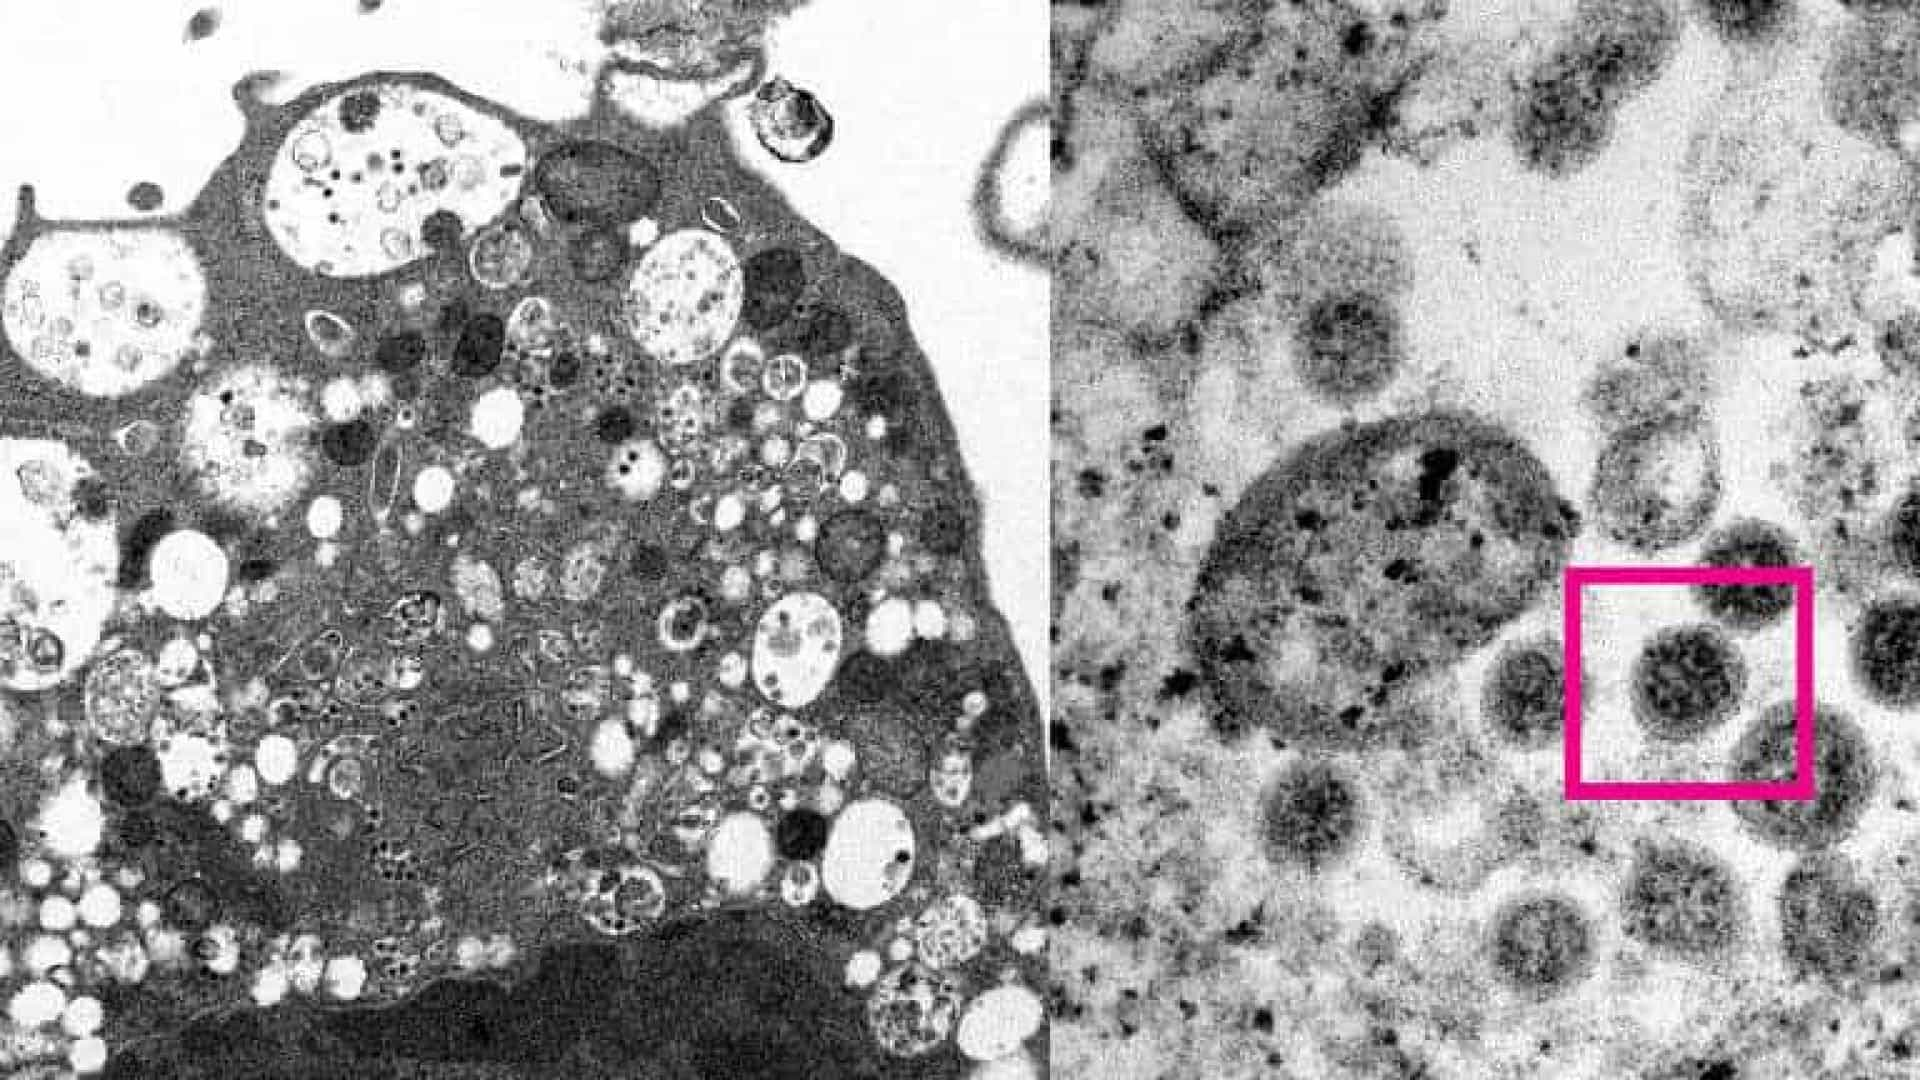

Segundo informações oficiais da instituição, os cientistas capturaram duas imagens da nova variante em microscópio.

À esquerda da imagem, é possível ver uma célula de um rim de macaco após infecção com a variante ômicron. A foto mostra alguns danos celulares com vesículas inchadas e contém pequenas partículas virais em cor preta.

Já a parte direita da imagem, vê-se uma célula infectada. Na parte que tem uma caixa vermelha, observa-se partículas virais com pontas em forma de coroa.